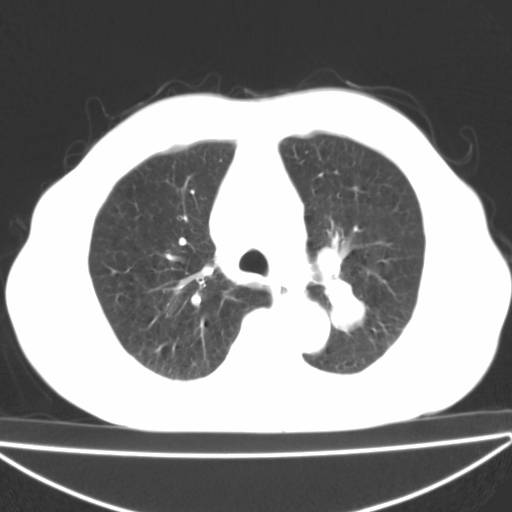

以下是引用zjzjr在2006-12-6 19:04:00的发言:[br]左肺上叶尖后段可见椭圆形高密度影,其内可见点状钙化影,周围可见卫星病灶.首先考虑结核,双侧少量胸腔积液.

以下是引用李世军在2006-12-6 19:54:00的发言:[br]左肺上叶尖后段可见椭圆形高密度影,其内可见点状钙化影,周围可见卫星病灶.首先考虑结核,双侧少量胸腔积液. [br] [br] 双肺轻度肺气肿,左肺上叶后段见多发斑片状密度增高影,周围见少许斑点状卫星病灶,双侧胸膜增厚粘连,纵隔内未见明显改变,考虑结核可能性大,请结合临床或增强扫描. [br] [br]

以下是引用13081830109在2006-12-6 19:35:00的发言:[br]左肺上叶尖后段可见椭圆形高密度影,其内可见点状钙化影,周围可见卫星病灶.首先考虑结核,双侧少量胸腔积液.